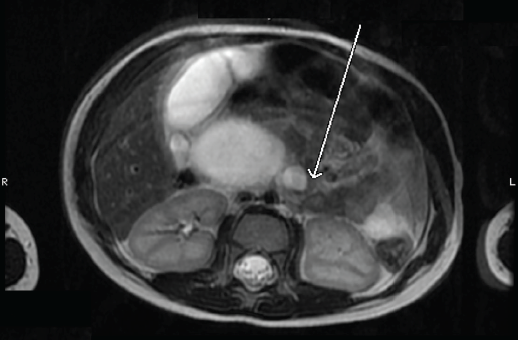

Magnetic resonance cholangiopancreatography (MRCP) confirmed the presence of extensive dilation of the intrahepatic and extrahepatic bile ducts (Figures 1 and 2). The patient received a diagnosis of a type IVa biliary cyst.

Figure 2. MRCP image of the extrahepatic choledochal cyst. The arrow indicates where the common bile duct enters the duodenum, which is displaced and compressed.